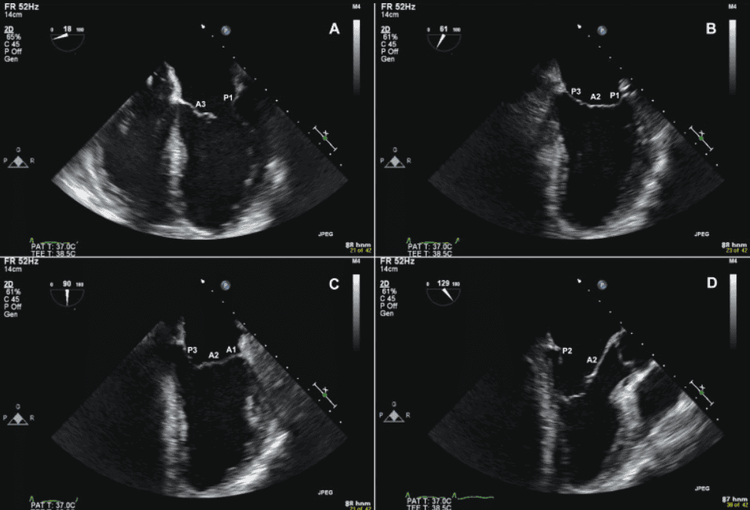

- Siêu âm tim qua thành ngực: Giúp thăm dò cấp đối với PTĐMC. Loại siêu âm này nhanh và không xâm; độ nhạy 80-100% giúp chẩn đoán Type A chính xác hơn. Tuy nhiên, đối với Type B độ nhạy, đặc hiệu thấp và thường khó xác định nguyên nhân, mức độ.

- Siêu âm qua thực quản: Đây là phương pháp chẩn đoán lý tưởng cũng an toàn và nhanh giúp xác định được nguyên nhân, mức độ lan với độ nhạy 94 - 100% và đặc hiệu 77 - 100%. Tuy nhiên, đây là phương pháp xâm lấn nên người bệnh cần phải an thần. Siêu âm tim qua thực quản khó có thể phát hiện các bệnh liên quan đến vùng giữa khí quản – thực quản